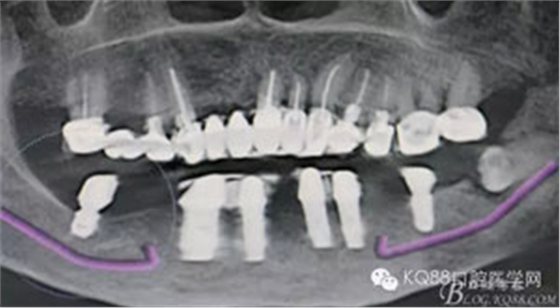

圖2.術(shù)前的CBCT影像檢查:38牙根尖靠近下頜神經(jīng)管。該CBCT是未帶烤瓷冠之前拍的。